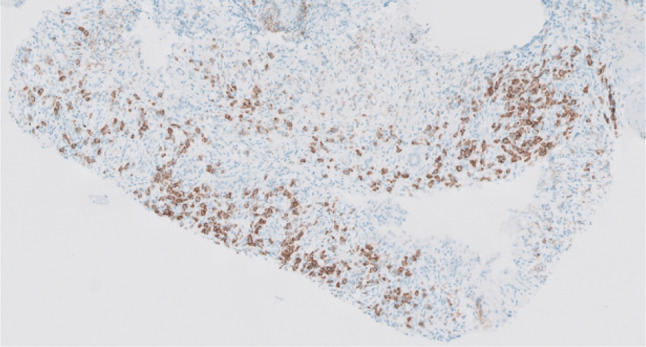

Case presentation: A 71-year-old male with malignant melanoma (BRAF wild-type) initially received one cycle of adjuvant pembrolizumab, followed by four cycles of ipilimumab/nivolumab after the occurrence of lung metastases. Four months later, a follow-up computed tomography (CT) revealed infiltrative masses in the kidneys, along with abnormal mediastinal and hilar lymphadenopathy but his baseline serum creatinine remained stable. A subsequent kidney biopsy showed renal parenchyma with significant interstitial nephritis and an increase in IgG4-positive plasma cells, with no evidence of malignancy. Plasma IgG4 levels were elevated at 294 mg/dL (normal 11-157 mg/dL), and complement C4 level was low at < 8 mg/dL. In addition, the patient had an asymptomatic rise in lipase (105 U/L, normal 7-60 U/L), but had no other findings to suggest pancreatitis. The patient was started on prednisone 40 mg daily with a plan to taper. A follow-up CT scan performed four weeks later showed near-complete resolution of the previously observed mediastinal lymphadenopathy and bilateral infiltrative renal masses.